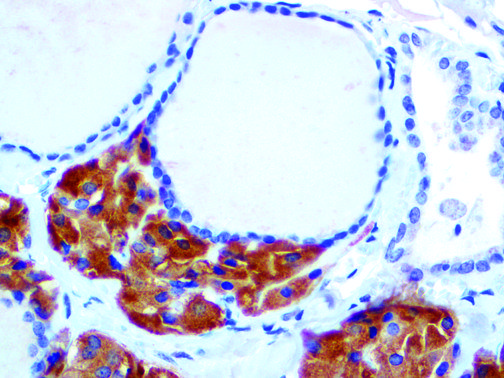

This activation induces inflammatory monocytes to highly express IL-6, starting a localized and then systemic cascade effect that results in hyperproduction of IL-6, which accelerates the inflammatory process. Because IL-6 also increases vascular permeability, excessive levels cause blood vessels to become very leaky. This, along with clotting factors released from vascular endothelial cells, stimulates the coagulation cascade, resulting in microthrombosis (tiny clots), which leads to ischemia and tissue death of the kidney, intestines, heart, liver, brain and extremities.